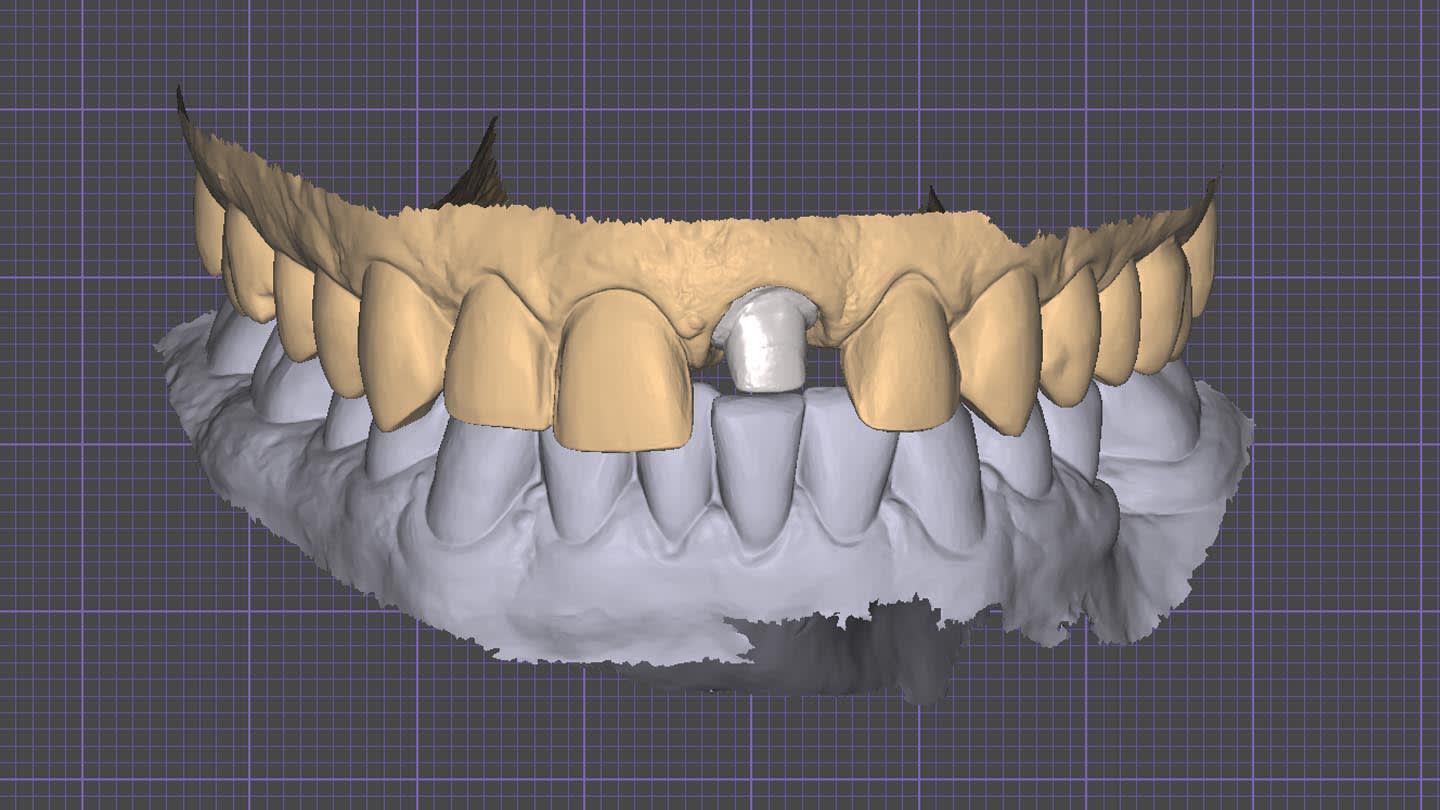

After crown removal on tooth No. 9, recontouring, and polishing, and veneer preparations of teeth Nos. 7, 8, and 10, the patient’s upper and lower arches were digitally scanned (TRIOS 4, 3Shape). These scans, along with digital photographs, were uploaded and integrated into the software (Digital Smile System SRL, digitalsmiledesign.com) for the virtual planning of the four veneers on teeth Nos. 7 through 10 and the opaque-core crown for No. 9 (Figure 4 through Figure 6). Ceramics with medium or high opacity, intended for the fabrication of core structures, were appropriate for this case. A lithium disilicate–reinforced monochromatic ceramic block with high-opacity color for CAD/CAM technology (IPS e.max®, Ivoclar, ivoclar.com) was used to fabricate the core for tooth No. 9. Then, it was fired in an oven (Zubler Vario Press 300, Jensen Dental, jensendental.com) for 5 minutes at 750°C and for 10 minutes at 850°C to complete crystallization, according to the manufacturer’s recommendations.

The opaque-core crown was tried-in on tooth No. 9 and approved in terms of marginal fit, preparation adaptation, and shade matching with the adjacent incisors. After this assessment, the crown was prepared, similar to the remaining teeth, to receive a ceramic veneer. A new digital intraoral final impression (TRIOS 4) was made for all four maxillary incisors, and the standard tessellation language (STL) files were sent to the laboratory for the manufacture of lithium-disilicate porcelain veneers (IPS e.max) using subtractive milling technology (PrograMill® PM5, Ivoclar). All data transfer from 3D planning to the laboratory CAD/CAM process is faster, easier, and more predictable than conventional methods, resulting in less manufacturing time and chairtime and enhanced final esthetic results (Figure 7 and Figure 8).16-18